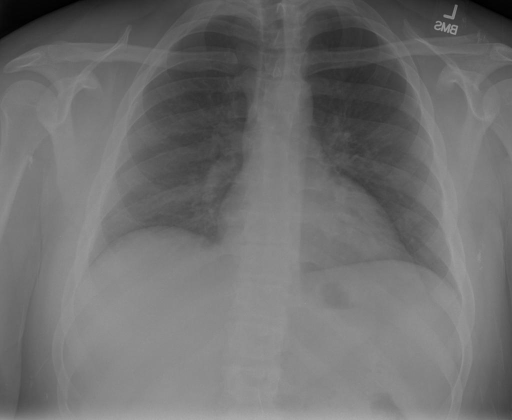

## 本文贡献  - 借助ChatGPT以及公开的数据集,我们构造了一个`X光影像-诊断报告`对的医学多模态数据集; - 我们将构建的中文胸部X光片诊断数据集在[VisualGLM-6B](https://github.com/THUDM/VisualGLM-6B)进行微调训练,并开放了部分训练权重用于学术研究; ## 数据集 - [MIMIC-CXR](https://physionet.org/content/mimic-cxr-jpg/2.0.0/)是一个公开可用的胸部X光片数据集,包括377,110张图像和227,827个相关报告。 - [OpenI](https://openi.nlm.nih.gov/faq#collection)是一个来自印第安纳大学医院的胸部X光片数据集,包括6,459张图像和3,955个报告。 在上述工作中,报告信息都为非结构化的,不利于科学研究。为了生成合理的医学报告,我们对两个数据集进行了预处理,并最终得到了可以用于训练的**英文报告**。除此之外,为了更好的支持中文社区发展,借助ChatGPT的能力,我们将英文报告进行了中文翻译,并最终形成了可用于训练的数据集。 |数据集|数量|下载链接| |:-|:-|:-| |MIMIC-CXR-zh|-|-| |OpenI-zh|6,423|[诊疗报告(英文)](./data/openi-en.json)、[诊疗报告(中文)](./data/Xray/openi-zh.json) 、[X光影像](https://pan.baidu.com/s/13GBsDMKf6xBZBSHpoWH_EA?pwd=k9sh)| ## 快速上手 1. 安装环境 ```bash # 安装依赖 pip install -r requirements.txt # 国内换源安装依赖 pip install -i https://mirrors.aliyun.com/pypi/simple/ -r requirements.txt ``` 此时默认会安装`deepspeed`库(支持`sat`库训练),此库对于模型推理并非必要,同时部分`Windows`环境安装此库时会遇到问题。 如果想绕过`deepspeed`安装,我们可以将命令改为: ```bash # 安装依赖 pip install -i https://mirrors.aliyun.com/pypi/simple/ -r requirements_wo_ds.txt # 安装SwissArmyTransformer pip install -i https://mirrors.aliyun.com/pypi/simple/ --no-deps "SwissArmyTransformer>=0.3.6" ``` 2. 模型推理 |模型权重|下载链接| |:-|:-| |checkpoints-XrayGLM-300|-| |checkpoints-XrayGLM-3000|-| CLI推理: ```python python cli_demo.py --from_pretrained checkpoints/checkpoints-XrayGLM-3000 --prompt_zh '详细描述这张胸部X光片的诊断结果' ``` 更多[参数](https://github.com/WangRongsheng/XrayGLM/blob/main/cli_demo.py#L16) ## 效果展示 影像诊断: |X光影像|诊疗报告(医生)|XrayGLM| |:-|:-|:-| ||根据X射线图像,心脏大小正常,肺部看起来很清晰。已经排除了肺炎、积液、水肿、气胸、腺病、结节或肿块的存在。该发现表明一切正常。换句话说,总体印象是胸部正常。|X光片显示,心脏大小正常。肺部没有气胸或胸腔积液的证据。骨骼结构看起来没有任何异常。总的来说,X光片表明没有发现急性心肺疾病的迹象。| ||X光图片显示没有扭曲的区域、可疑的骨质不透明度或胸腺积液。心脏大小轻微增大,但非常稳定。此外,没有气胸的证据,肺野也正常。总体来说,X光片显示没有急性心脏异常,但要注意轻微的心脏扩大。|X光片显示,心脏大小正常。肺部和纵隔轮廓清晰,没有气胸或胸腔积液的证据。骨骼结构完整,没有任何急性异常。| ||心影形态在正常范围内。没有急性骨质异常。有可能出现没有明显的吸水或肺实质状况的线索。没有大面积积液或气胸。有可能怀疑其有误吸或肺实质问题。为了确诊和治疗,可能需要进行适当的影像学随访。|心脏大小正常,肺部和纵隔轮廓清晰。没有急性异常或活动受限的证据。没有任何明显的气胸、胸腔积液或肺不张的迹象。此外,也没有发现任何局灶性骨质异常或其他急性疾病。| 多轮对话: |X光影像|诊疗报告(医生)| |:-|:-| ||右侧主动脉突出观察到。心脏大小正常。胸部未发现明显的肺气肿、胸膜积液或可疑的肺部病变。报告指出已知右侧主动脉情况正常。| ```bash >> X光影像路径:./data/Xray/861_1.png >> 用户:这是一张什么图? >> XrayGLM:这张图片显示的是一张肺部检查的X光片。 >> 用户:请描述这张胸部X光片的诊断结果 >> XrayGLM:心脏大小正常,肺部清晰。没有急性心肺疾病的证据。 >> 用户:是否存在肺气肿? >> XrayGLM:没有肺气肿。心脏大小正常,肺部清晰。没有发现急性心肺疾病的证据。 >> 用户:平时饮食该注意什么? >> XrayGLM:饮食应该健康,均衡。建议增加蛋白质的摄入量,因为蛋白质有助于维持肌肉和骨骼的健康。多食用蔬菜、水果、全谷物以及健康的脂肪来源如橄榄油、鱼类等可以帮助获得足够的维生素和矿物质。此外,避免过度饮酒或吸烟,这些习惯可能会对心脏健康产生负面影响。 ``` ## 未来展望 1. 模型的能力更多来源于数据的支持,`OpenI-zh`作为微调数据集,其数据量足以支持研究,在更广泛的任务和性能表现上,我们认为**在大规模数据集上预训练并在高质量少量数据集上微调是一种可行的方案**; 2. 普遍意义的理解上,视觉多模态模型=视觉模型+语言模型。除了需要关注视觉模型信息与语言模型输出的搭配外,还需要**额外关注到语言模型的加强,在人机的对话中,尤其是医疗语言模型的问答上,除了专业的医疗问题回答,带有人文情怀的有温度的回答更应该是我们追寻的目标**。 ## 项目致谢 1. [VisualGLM-6B](https://github.com/THUDM/VisualGLM-6B)为我们提供了基础的代码参考和实现; 2. [MiniGPT-4](https://github.com/Vision-CAIR/MiniGPT-4)为我们这个项目提供了研发思路; 3. ChatGPT生成了高质量的中文版X光检查报告以支持XrayGLM训练; 4. [gpt_academic](https://github.com/binary-husky/gpt_academic)为文档翻译提供了多线程加速; 5. [MedCLIP](https://github.com/RyanWangZf/MedCLIP) 、[BLIP2](https://huggingface.co/docs/transformers/main/model_doc/blip-2) 、[XrayGPT](https://github.com/mbzuai-oryx/XrayGPT) 等工作也有重大的参考意义;  这项工作由[澳门理工大学应用科学学院](https://www.mpu.edu.mo/esca/zh/index.php)硕士生[王荣胜](https://github.com/WangRongsheng) 、[段耀菲](https://github.com/IsBaSO4) 、[李俊蓉](https://github.com/lijunrong0815)完成,指导老师为檀韬副教授、[彭祥佑](http://www.patrickpang.net/)老师。 *特别鸣谢:[USTC-PhD Yongle Luo](https://github.com/kaixindelele) 提供了有3000美金的OpenAI账号,帮助我们完成大量的X光报告翻译工作 ## 免责声明 本项目相关资源仅供学术研究之用,严禁用于商业用途。使用涉及第三方代码的部分时,请严格遵循相应的开源协议。模型生成的内容受模型计算、随机性和量化精度损失等因素影响,本项目无法对其准确性作出保证。即使本项目模型输出符合医学事实,也不能被用作实际医学诊断的依据。对于模型输出的任何内容,本项目不承担任何法律责任,亦不对因使用相关资源和输出结果而可能产生的任何损失承担责任。 ## 项目引用 如果你使用了本项目的模型,数据或者代码,请声明引用: ```bash @misc{wang2023XrayGLM, title={XrayGLM: The first Chinese Medical Multimodal Model that Chest Radiographs Summarization}, author={Rongsheng Wang, Yaofei Duan, Junrong Li, Patrick Pang and Tao Tan}, year={2023}, publisher = {GitHub}, journal = {GitHub repository}, howpublished = {\url{https://github.com/WangRongsheng/XrayGLM}}, } ``` ## 使用许可 此存储库遵循[CC BY-NC-SA](https://creativecommons.org/licenses/by-nc-sa/4.0/) ,请参阅许可条款。